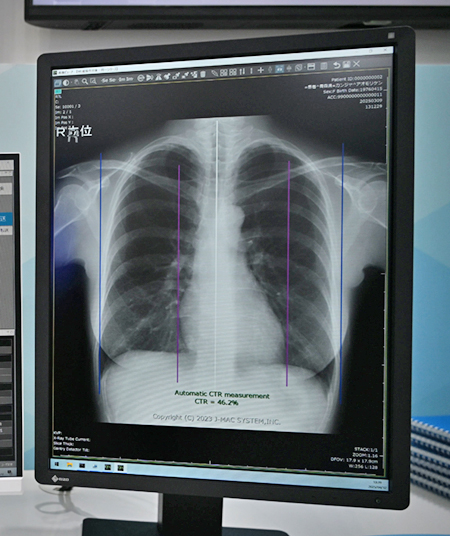

CTR計測は,胸部単純X線画像から心胸郭比を自動で算出して,心拡大の判定のための情報を提供する。手動での測定,計算するよりも作業が効率化され,計測時間を短縮。医師や診療放射線技師の業務負担を軽減する。

「CTR計測」はAI技術で心胸郭比を自動で算出